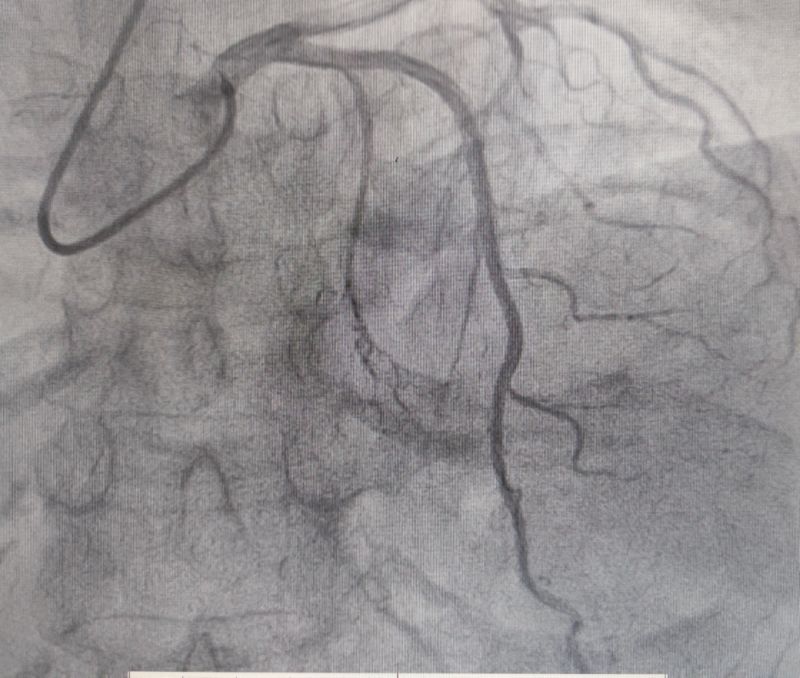

冠脈造影

經(jīng)過多輪嚴(yán)謹(jǐn)?shù)男g(shù)前討論,在吳棟梁院長的專業(yè)指導(dǎo)下,崔旭輝主任醫(yī)師團(tuán)隊決定在臨時起搏器的安全保護(hù)下,為患者實施冠狀動脈造影術(shù)及室間隔化學(xué)消融術(shù)。術(shù)中,團(tuán)隊通過造影精準(zhǔn)鎖定第一穿隔支為消融靶血管。測壓數(shù)據(jù)顯示:左室壓260/15mmHg,流出道173/6mmHg,主動脈壓106/70 mmHg,壓力階差達(dá)87mmHg。隨后,團(tuán)隊使用2.0X15mm預(yù)擴(kuò)球囊以8atm壓力阻斷第一穿隔支遠(yuǎn)端血流1分鐘,再次測壓時,壓力從269/7mmHg驟降至174/4mmHg,這一結(jié)果充分證實該血管正是室間隔的有效供血血管。緊接著,團(tuán)隊通過SPRINTER OTW2.0×8mm球囊緩慢注入1.4ml無水酒精。10分鐘后復(fù)測,左心室壓降至136/5 mmHg,主動脈壓為112/93 mmHg。術(shù)后第2天,王女士胸悶、氣短、心悸等不適癥狀完全消失。復(fù)查心臟彩超顯示:EF值與FS值保持穩(wěn)定,收縮期左室流出道血流速度降至252cm/s,PG值為25mmHg。